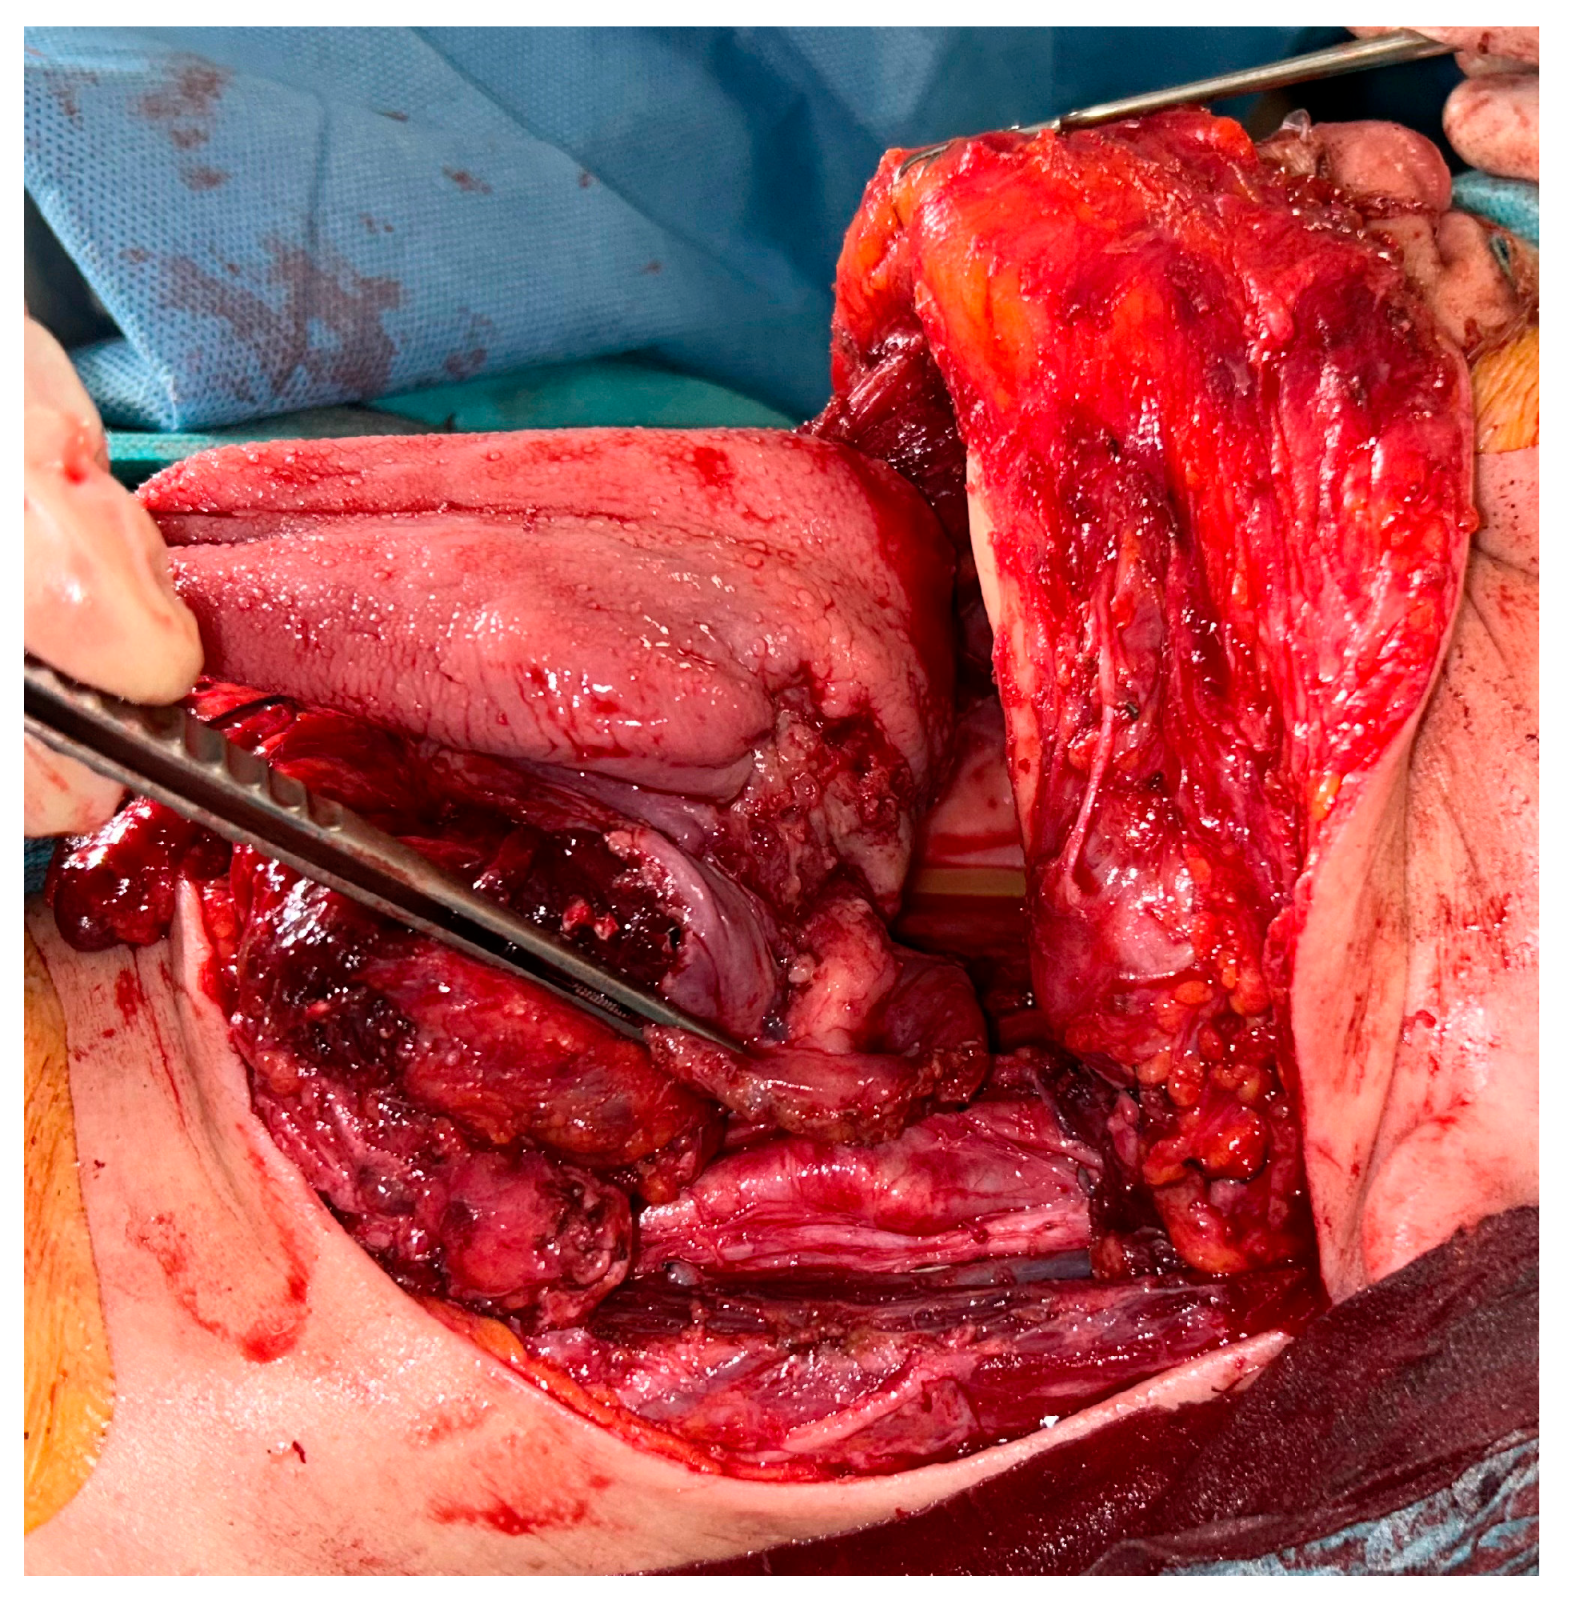

2. Detailed Case Description